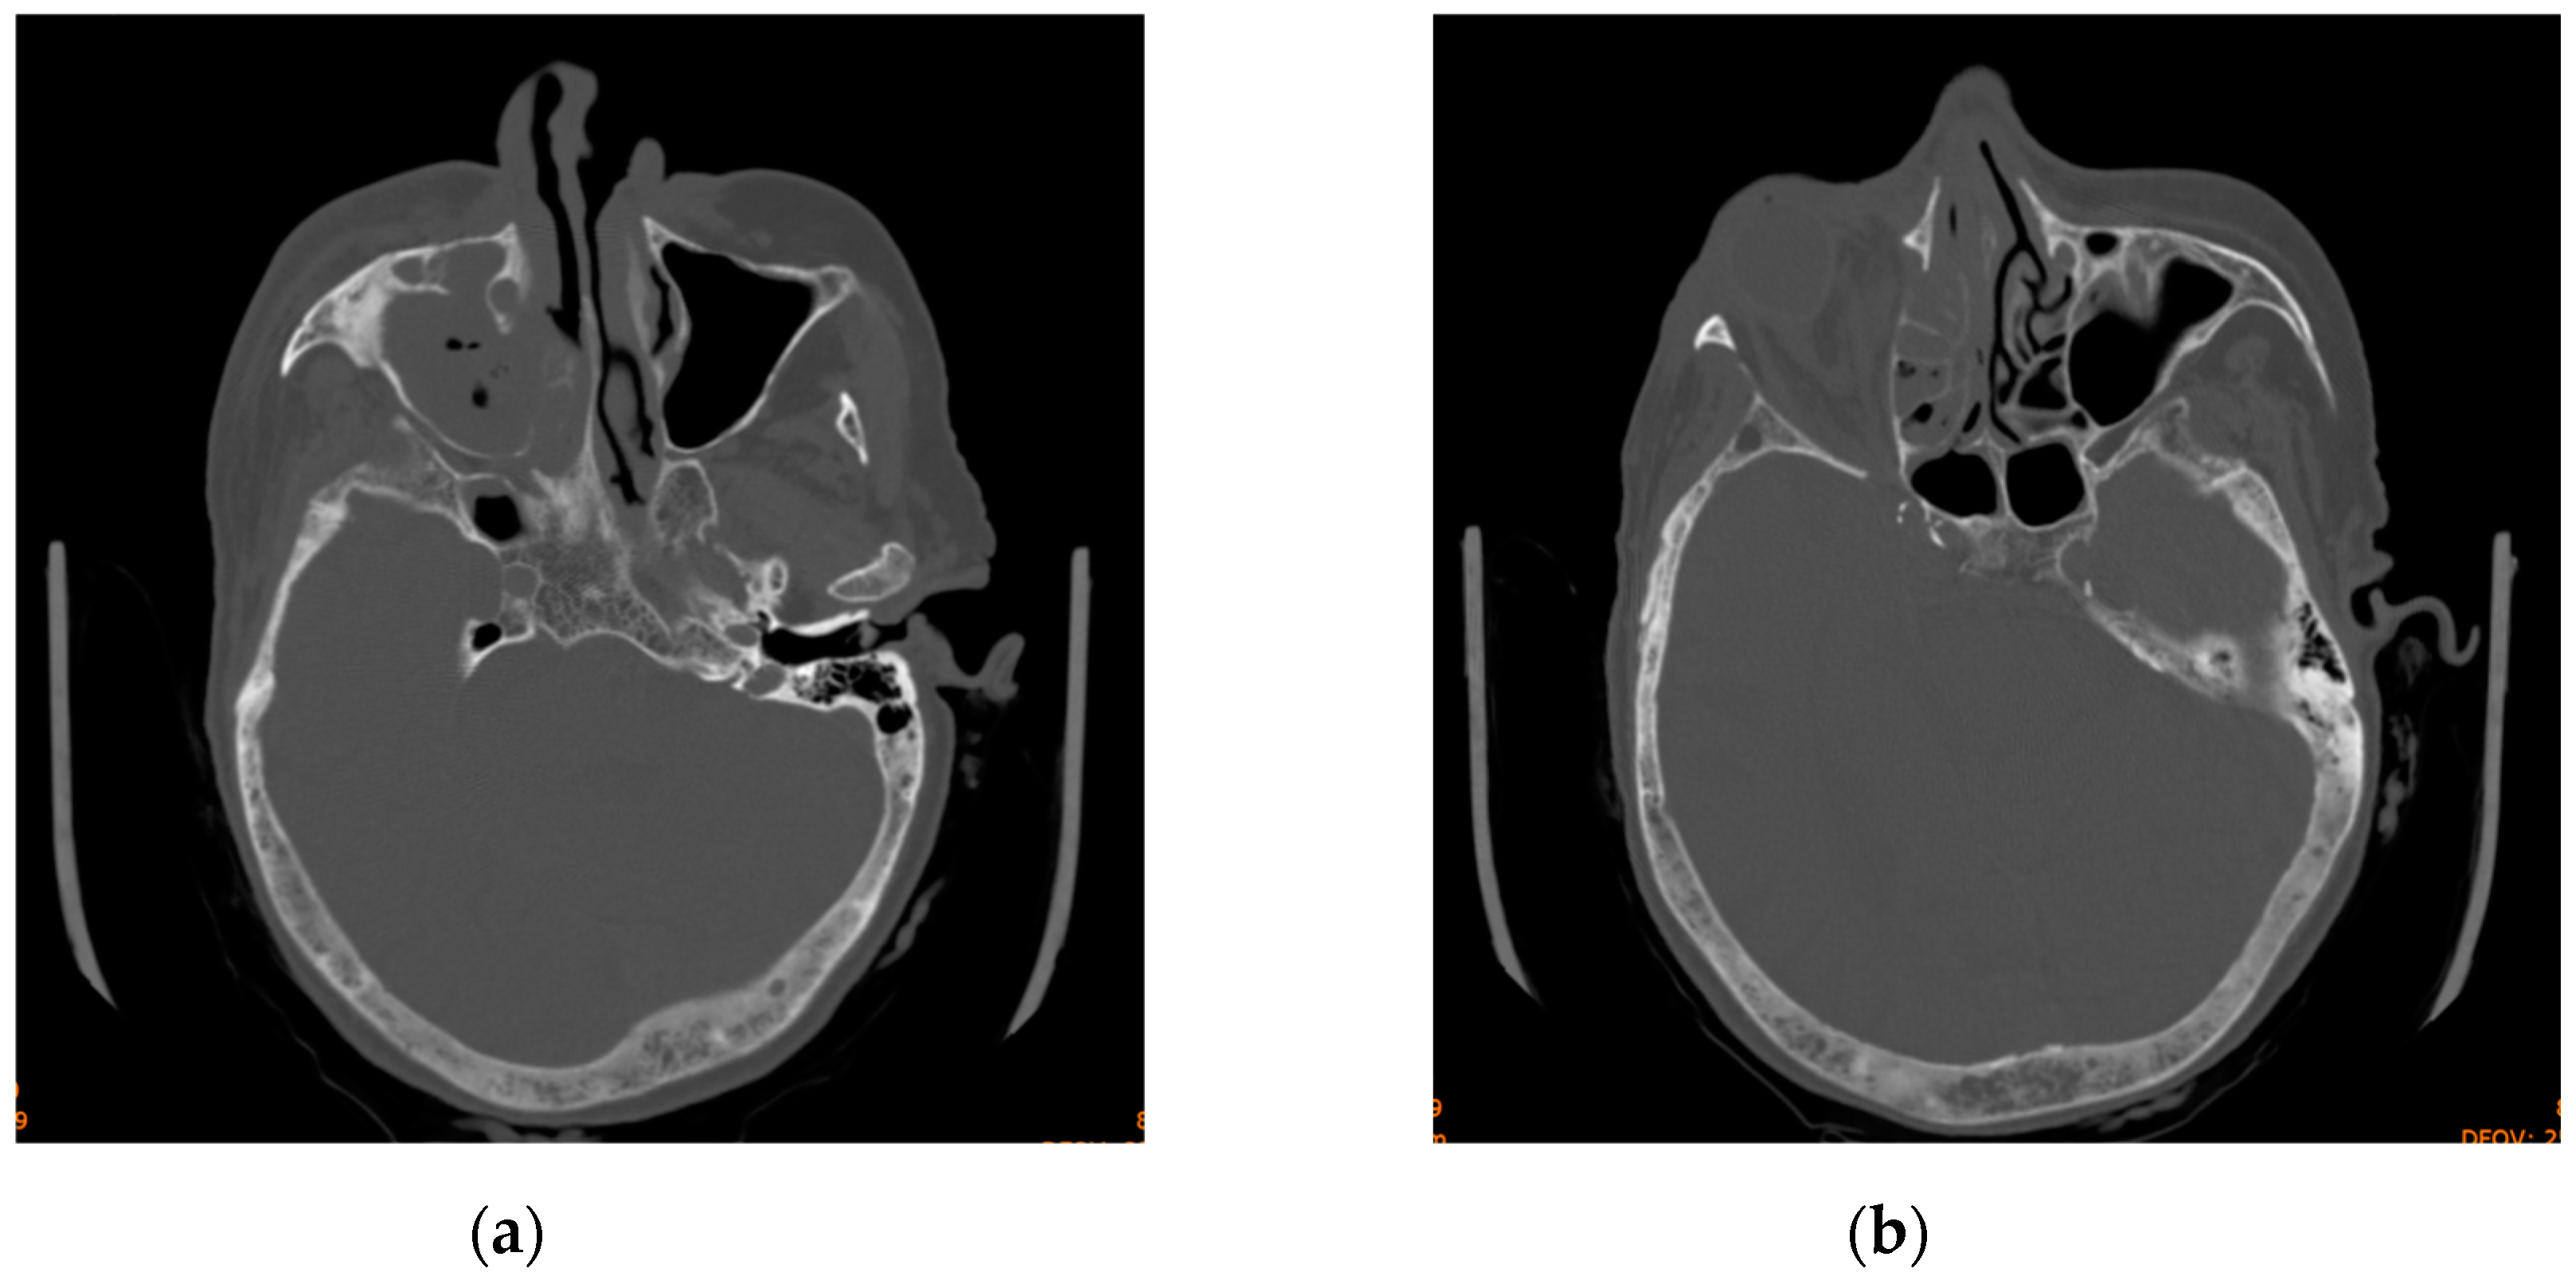

The head CT revealed right-sided orbital abscess with reticulation of the fat, pansinusitis with maxillary and ethmoid sinus opacification (Figure 2), multiple gas bubbles extending from the ethmoidal cells to the right orbit, a stretched right optic nerve, and posterior globe tenting (Figure 3). The abscess in the right canine space originated from the buccal roots of teeth 13 and 15. The fluid collection extended continuously from the right canine space upward and backward to the right lateral orbit.

Figure 3. Computed tomography scan displaying maxillary and ethmoid sinus opacification, multiple gas bubbles extending from the ethmoidal cells to the right orbit, a stretched right optic nerve, and posterior globe tenting: (a) axial section; (b) coronal section.